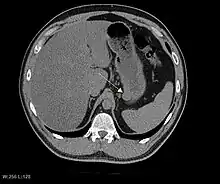

The purpose of radiologic imaging is to locate the lesion, evaluate for signs of invasion and detect metastasis. Features of GIST vary depending on tumor size and organ of origin. The diameter can range from a few millimeters to more than 30 cm. Larger tumors usually cause symptoms in contrast to those found incidentally which tend to be smaller and have better prognosis.[4][13] Large tumors tend to exhibit malignant behavior but small GISTs may also demonstrate clinically aggressive behavior.[14]

Barium fluoroscopic examinations and CT are commonly used to evaluate the patient with abdominal complaints. Barium swallow images show abnormalities in 80% of GIST cases.[14] However, some GISTs may be located entirely outside the lumen of the bowel and will not be appreciated with a barium swallow. Even in cases when the barium swallow is abnormal, an MRI or CT scan must follow since it is impossible to evaluate abdominal cavities and other abdominal organs with a barium swallow alone. In a CT scan, abnormalities may be seen in 87% of patients and it should be made with both oral and intravenous contrast.[14] Among imaging studies, MRI has the best tissue contrast, which aids in the identification of masses within the GI tract (intramural masses). Intravenous contrast material is needed to evaluate lesion vascularity.

Preferred imaging modalities in the evaluation of GISTs are CT and MRI,[16]: 20–21 and, in selected situations, endoscopic ultrasound. CT advantages include its ability to demonstrate evidence of nearby organ invasion, ascites, and metastases. The ability of an MRI to produce images in multiple planes is helpful in determining the bowel as the organ of origin (which is difficult when the tumor is very large), facilitating diagnosis.

As the tumor grows it may project outside the bowel (exophytic growth) and/or inside the bowel (intraluminal growth), but they most commonly grow exophytically such that the bulk of the tumor projects into the abdominal cavity. If the tumor outstrips its blood supply, it can necrose internally, creating a central fluid-filled cavity with bleeding and cavitations that can eventually ulcerate and communicate into the lumen of the bowel. In that case, barium swallow may show an air, air-fluid levels or oral contrast media accumulation within these areas.[14][17] Mucosal ulcerations may also be present. In contrast-enhanced CT images, large GISTs appear as heterogeneous masses due to areas of living tumor cells surrounding bleeding, necrosis or cysts, which is radiographically seen as a peripheral enhancement pattern with a low attenuation center.[13] In MRI studies, the degree of necrosis and bleeding affects the signal intensity pattern. Areas of bleeding within the tumor will vary its signal intensity depending on how long ago the bleeding occurred. The solid portions of the tumor are typically low signal intensity on T1-weighted images, are high signal intensity on T2-weighted images and enhanced after administration of gadolinium. Signal-intensity voids are present if there is gas within areas of necrotic tumor.[15][18][19]

Features of malignancy

Malignancy is characterized by local invasion and metastases, usually to the liver, omentum and peritoneum. However, cases of metastases to bone, pleura, lungs and retroperitoneum have been seen. In distinction to gastric adenocarcinoma or gastric/small bowel lymphoma, malignant lymphadenopathy (swollen lymph nodes) is uncommon (<10%) and thus imaging usually shows absence of lymph node enlargement.[13] If metastases are not present, other radiologic features suggesting malignancy include: size (>5 cm), heterogeneous enhancement after contrast administration, and ulcerations.[4][13][20] Also, overtly malignant behavior (in distinction to malignant potential of lesser degree) is less commonly seen in gastric tumors, with a ratio of behaviorally benign to overtly malignant of 3-5:1.[4] Even if radiographic malignant features are present, these findings may also represent other tumors and definitive diagnosis must be made immunochemically.